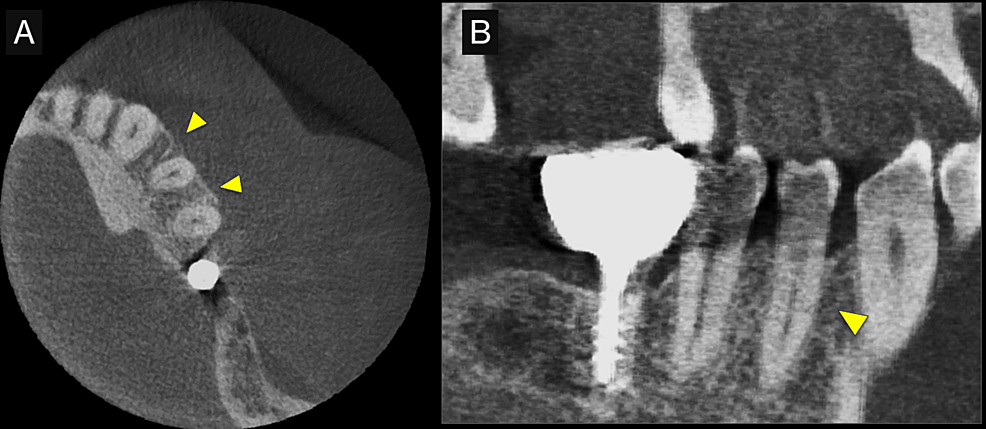

First, initial treatment including oral hygiene instruction was provided, followed by scaling and root planing. Teeth #16, #27, #37, and #46 were extracted, as they were considered too difficult to preserve. After reevaluation, a dental implant was provided for tooth #46. The patient was enrolled in supportive periodontal therapy after it was confirmed that the initial course of periodontal treatment had stabilized conditions. Subsequently, an acute periodontal abscess was observed in #44, however, requiring the start of anti-inflammatory treatment including periodontal pocket curettage under local anesthesia and oral antibiotics. Nevertheless, no improvement was found in the 6-mm buccal pocket of #44, so periodontal tissue regeneration therapy was planned. Before starting such treatment, in addition to intraoral radiography, cone-beam computed tomography (CBCT) was also performed using the 3DX Multi Image Micro CT (J MORITA Co., Ltd., Kyoto, Japan) (Figures 1, 2). The scan parameters were as follows: 90-kV tube voltage; 7-mA tube current; field of view, 60 mm x 60 mm; and slice thickness, 0.125 mm. The CBCT images revealed an intrabony, two-walled, defect around #44 that was slightly less radiolucent on the intraoral radiographic image. It was localized on the buccal side from the proximal to the distal aspect. A relatively large mandibular torus interior was also observed on the lingual side of #44 and #43.

Intraoral radiography and CBCT scanning were performed 14 months postoperatively (Figures 4, 5). The results were displayed on a personal computer monitor screen, and the morphology of the bone at the surgical site and its internal structure was observed in 3D, by which the regrowth of bone-like structures at the site of the intrabony defect was confirmed. At two years postoperatively, no subjective symptoms such as pain or objective signs such as tooth movement or gingival recession were observed. No other notable findings or abnormalities were observed, and the postoperative course was judged to be good.